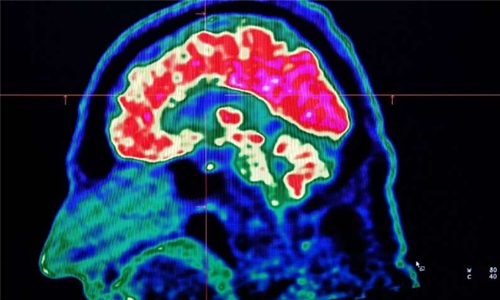

A new study published in Cell Reports on Tuesday honed in on the brain circuitry responsible for upgrading or downgrading these pain signals, likening the mechanism to how a home thermostat controls room temperature. Yarimar Carrasquillo, the paper’s senior author and a scientist for the National Center for Complementary and Integrative Health (NCCIH), said the region responsible was the central amygdala, which according to her work appeared to play a dual role.

Studying mice, Carrasquillo and her colleagues found that the activity in neurons that express protein kinase C-delta amplified pain, while neurons that express somatostatin inhibited the chain of activity in the nerves required to communicate pain. The central amygdala isn’t completely responsible for pain itself: if it were removed entirely, then “the ‘ouch’ of things, or the protective pain, would remain intact,” said Carrasquillo.